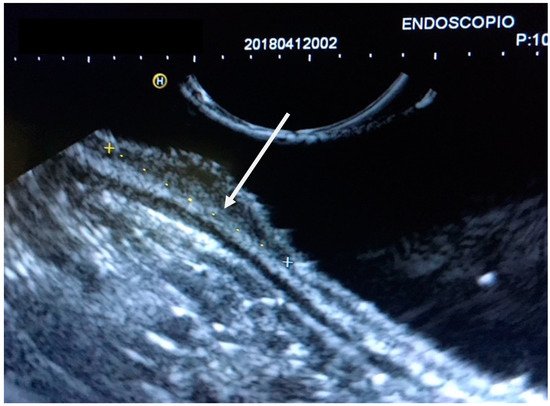

3. EUS Technique